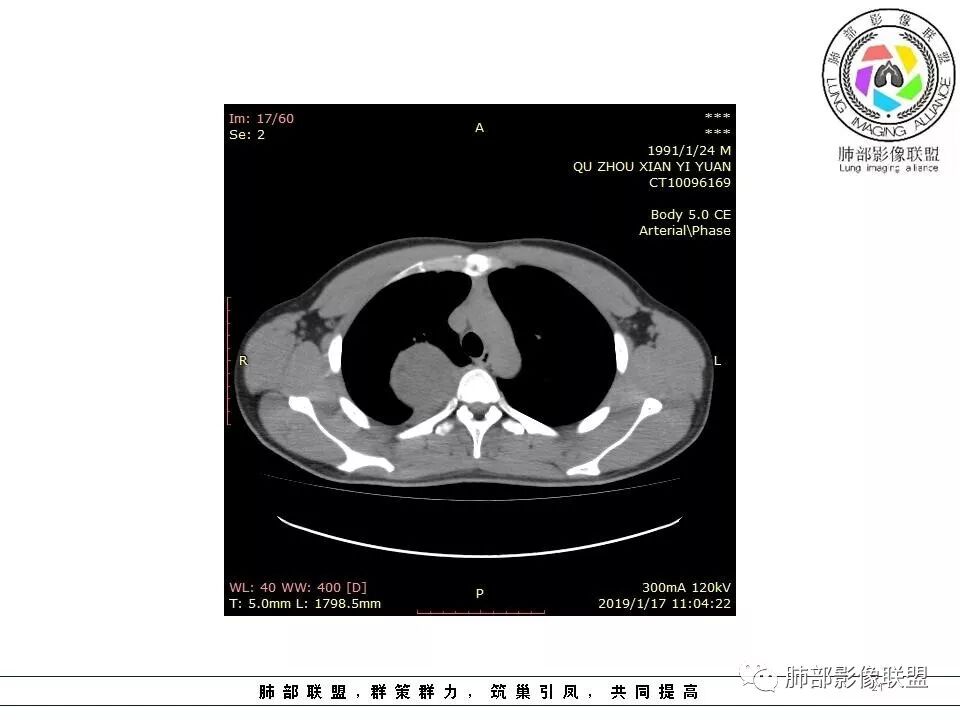

右后纵膈脊柱旁软组织占位,形态规则类圆,边缘光整,肺组织受压,胸膜尾,肋间动脉供血。中度不均匀延迟强化。

后纵隔脊柱旁占位性病变,疾病谱有神经鞘瘤,sft,节细胞瘤,髓外造血。此例有胸膜尾征,蛇纹征 ,延迟强化。考虑胸膜孤立性纤维瘤。看到有供血动脉,但不知道是哪里的血管。

后纵隔类圆形新生物,边缘光滑,胸膜尾征明显,贴近脊柱,蛇纹,血供丰富,考虑后纵隔软组织肿瘤,具体类型看不出来,鉴别神经鞘瘤。

右后纵膈脊柱旁软组织占位,边界清晰,光整,肺组织受压。胸膜被掀起,肋间动脉供血,中度不均匀延迟强化。考虑神经鞘瘤,不除外纤维瘤

右后纵膈脊柱旁软组织影,与纵隔结构分界不清,形态规则类圆,边缘光整,肺组织受压,胸膜尾,肋间动脉供血。肺动脉推移,中度不均匀延迟强化。考虑神经来源,神经鞘瘤,神经纤维瘤二者不易鉴别。

青年男性,间断胸痛;右侧脊柱旁可见一类圆形软组织密度影,密度欠均匀,增强扫描呈轻中度持续强化,邻近肺组织及肺动脉推移,可见肋间动脉供血,部分胸膜下脂肪可见,部分层面似见与右侧椎间孔相连。考虑后纵隔神经源性肿瘤。

后纵隔脊柱旁占位性病变,有胸膜尾征,胸膜下脂肪可见,蛇纹征,明显强化。考虑孤立性纤维瘤。

定位肺外。强化不均匀,散在血管。考虑sft,鉴别:神经鞘瘤,付节瘤,cd。鞘瘤有ab区,付节瘤高血压,cd强化,形态不支持。

病灶定位脏层胸膜,肺组织受挤压,有胸膜尾征,动脉期可见血管支配,考虑肺动脉供血,静脉期,强化增强明显,符合快进慢出特点,病灶内可见低密度区,考虑胸膜孤立纤维瘤。

右侧后纵隔脊柱旁占位,边缘光滑清晰,内侧肺组织受压,外侧可见胸膜尾征,增强持续强化,并可见蛇纹血管征。考虑SFT

青年男性,间断胸痛。右后纵膈脊柱旁软组织占位,形态规则类圆,边缘光整,肺组织受压,D字征,胸膜尾,肋间动脉供血。中度不均匀延迟强化。无支气管进入考虑来源于肺外、肿块与脊柱间未见明显脂肪间隙,考虑来源于胸膜外,考虑神经源性肿瘤,建议穿刺活检。

病例小结

1.右上胸内脊柱旁类圆形肿块,质地似乎比较坚实,密度稍显不均,但未显示明确的坏死。

如此密度形态的病灶位于肺边缘首先应当想到孤立性纤维瘤,可相邻胸膜未见明显的异常强化和胸膜方向延伸。

注意所谓“胸膜尾征”的概念及形成机制与“脑膜尾征”是大不相同的。

2.肋间动脉病供血也提示肿块来自后纵隔?

3.相邻椎间孔未见扩大,也未见块影延入椎管,易起自于神经根的鞘瘤似乎找不到支持点。

可惜未提供矢状位骨窗图像,如在肋骨内下缘观察到压迹有助于肋间神经的鞘瘤的判断,这是因为二者之间密切的毗邻关系。

4.静脉期轻度不均匀强化,注意不是环形强化,亦未见明确的“AB区”,这点也不支持神经鞘瘤。临床及病灶轻度强化都不支持副节瘤。